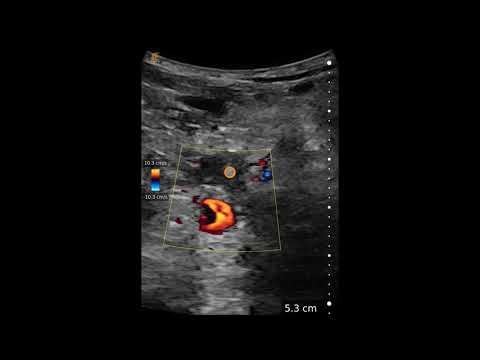

Temporal Artery Evaluation

Source: Clarius